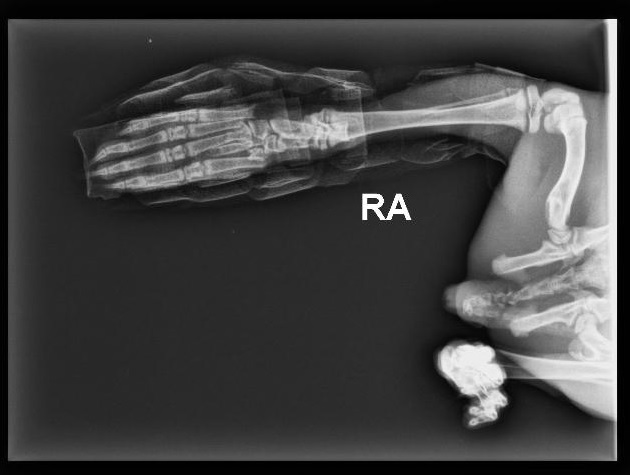

Een jong konijntje kwam in de spoeddienst op de praktijk toen ze slechts 5 maanden oud was. Per ongeluk had zij het konijnenhok op haar achterpoot gekregen en meteen twijfelden de eigenaars of zij een stuk bot uit de voet konden zien steken.

Tijdens het klinisch onderzoek werd dit vermoeden bevestigd. Er is een röntgenfoto gemaakt om te zien waar de breuk exact zat en of er andere botjes ook gebroken waren. Op de röntgenfoto bleken álle middenvoetsbeentjes te zijn gebroken...

Wat nu? Na overleg met een orthopeed, werd besloten om genezing te laten gebeuren met behulp van een spalk. De open wond was wel een risico op infectie, zodat deze regelmatig gecontroleerd is. Omdat het dier zo jong is, werd er gehoopt dat herstel snel zou optreden.

Drie weken later werd de röntgenfoto herhaald. Er was wel iets herstel opgetreden, maar nog niet zo ver als dat we hadden gehoopt. De spalk is nu af en ze mag proberen de poot een klein beetje te gebruiken, maar deze jonge dame heeft nog een reisje te gaan. Gelukkig is ze sterk en groeit ze als kool en we hopen dat de genezing helemaal volgens plan zal verlopen!